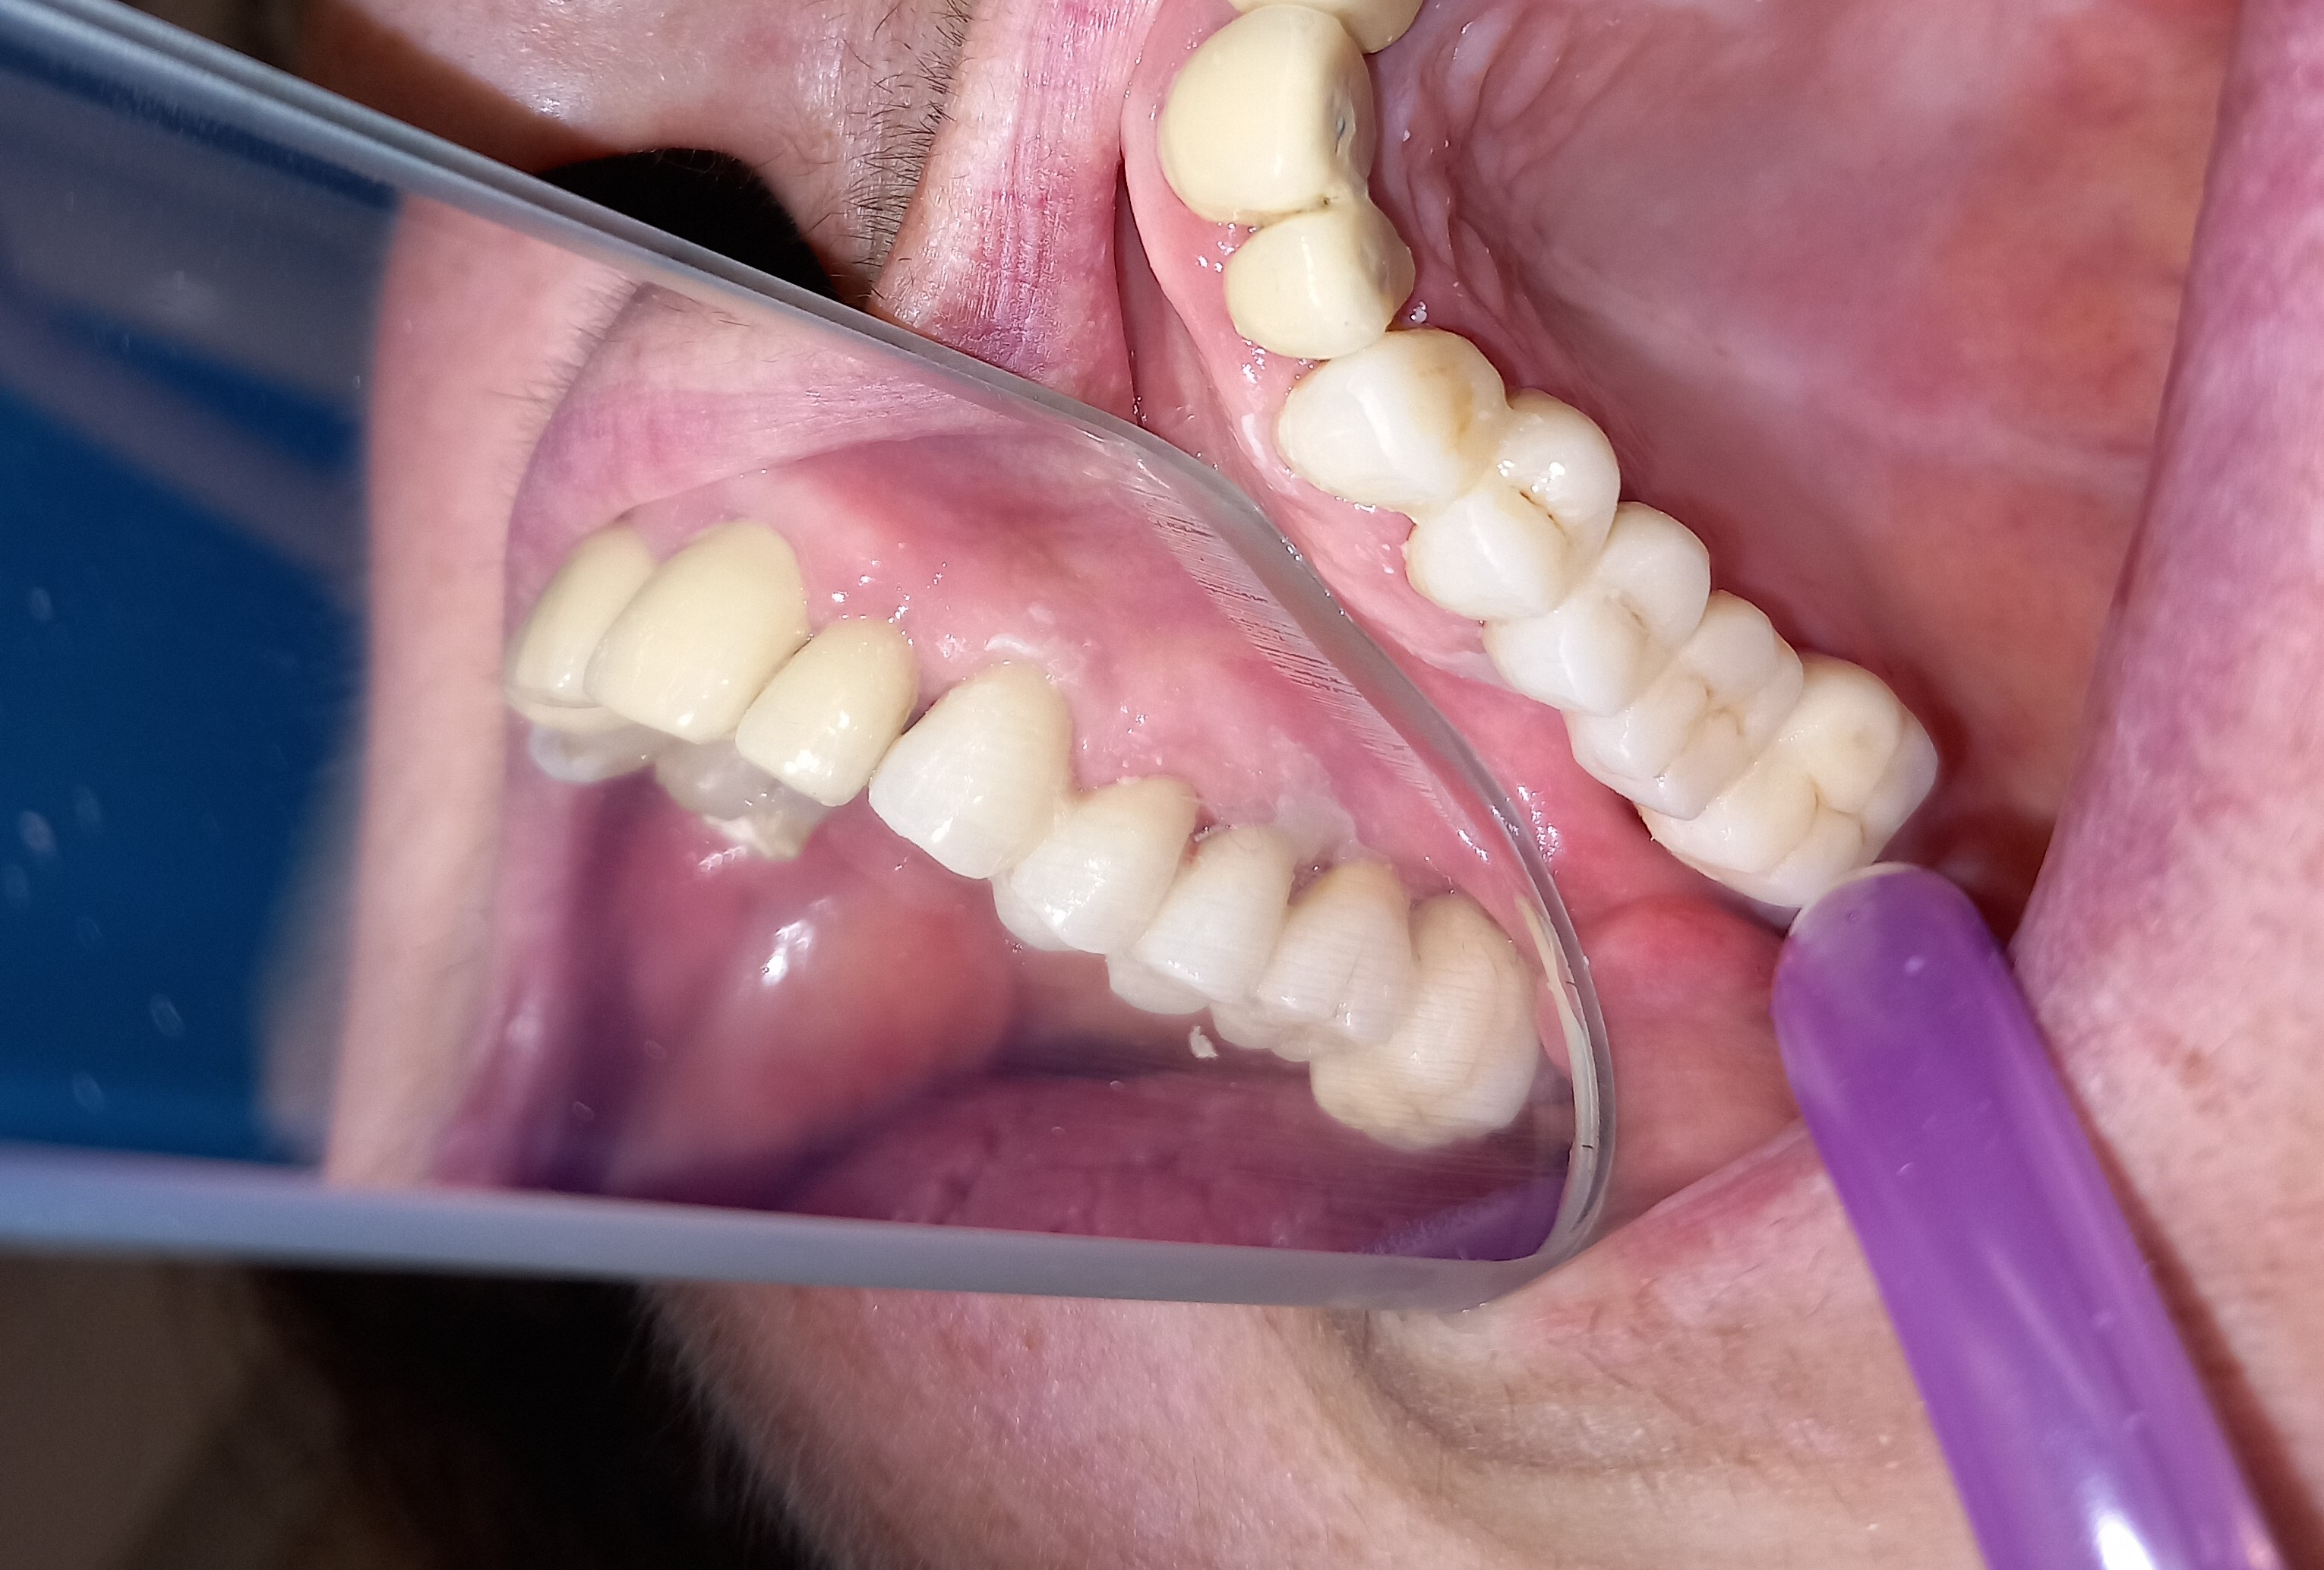

Ο ασθενής είχε πάρα πολλά χρόνια να επισκεφτεί τον οδοντίατρο. Πρόκειται για ένα απαιτητικό περιστατικό, κατά το οποίο ο ασθενής ήταν πολύ συνεργάσιμος καθώς ήθελε να αποκτήσει ένα όμορφο και λαμπερό χαμόγελο. Αρχικά εξάχθηκαν όσα δόντια δεν μπορούσαν να διατηρηθούν πλέον στο στόμα του ασθενή. Στη συνέχεια απονευρώθηκαν τα περισσότερα δόντια και ακολούθησαν ανασυστάσεις όλων των δοντιών. Εφόσον είχε αποκατασταθεί η φλεγμονή των ούλων λήφθηκαν αποτυπώματα και στάλθηκαν στον οδοντοτεχνίτη ο οποίος κατασκεύασε ολοκεραμικές θήκες, οι οποίες ήταν ενωμένες μεταξύ τους (ολοκεραμικό πέταλλο). Ο ασθενής φορούσε προσωρινή γέφυρα στο μεσοδιάστημα που χρειάστηκε ο οδοντοτεχνίτης να κατασκευάσει τη μόνιμη προσθετική εργασία.

Ο ασθενής είναι πολύ χαρούμενος με το λειτουργικό και αισθητικό του αποτέλεσμα. Πρέπει να αναφερθεί οτι όσο καιρό ο ασθενής δεν είχε δόντια δυσκολευόταν πολύ στην άρθρωση του λόγου.

Ολοκεραμικό πέταλο ζιρκονίου

ΜΕΤΑ